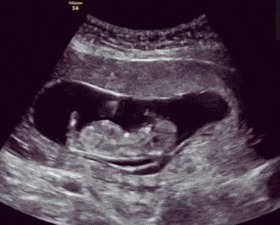

胎动,顾名思义就是胎儿在妈妈子宫里活动,比如伸手、蹬腿、翻身、打嗝等,触碰激烈时,妈妈就会有所感觉。一般而言,大多数的孕妇在孕4月开始感受到第一次胎动。